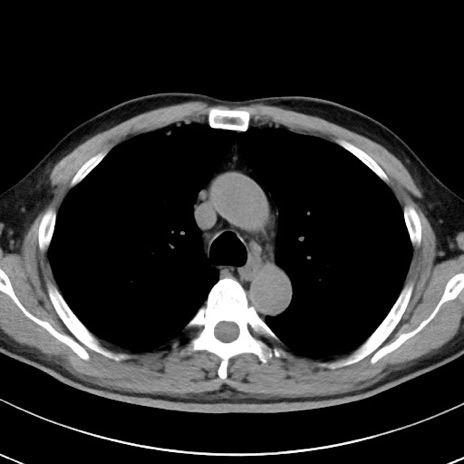

【腹部TIPS】症例29 参考症例 CT(横断像)

症例

70歳代男性